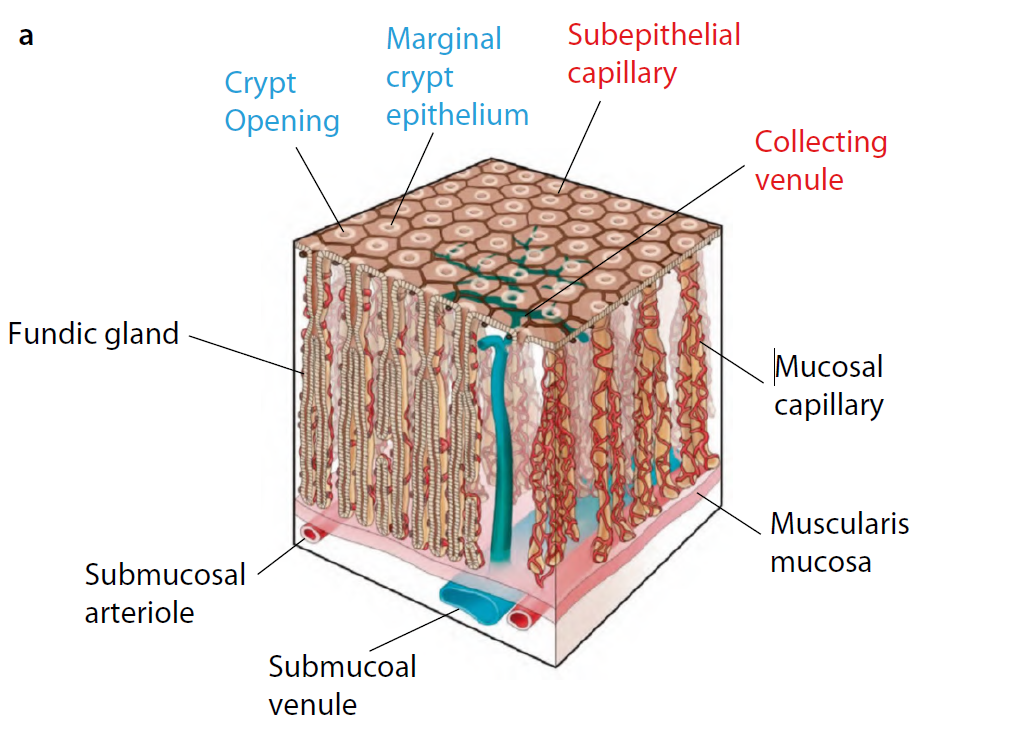

The VS classification system developed by the author (Kenshi Yao) [1] is the most widely accepted diagnostic system for magnifying narrowband imaging (M-NBI) of the stomach [2]. The VS classification system employs anatomical terms as endoscopic markers for analysis. Anatomical components visualized using M-NBI were divided into microvascular (MV) and microsurface (MS) patterns. As shown in . Fig. 1a–c, the subepithelial capillary and collecting venule were visualized for MV pattern, while the marginal crypt epithelium (MCE), crypt opening (CO), and intervening part (IP) between the crypts were identified for the MS pattern. In addition, in terms of the pathological status, the light blue crest [3] and white opaque substance [4] can be markers for microsurface patterns.